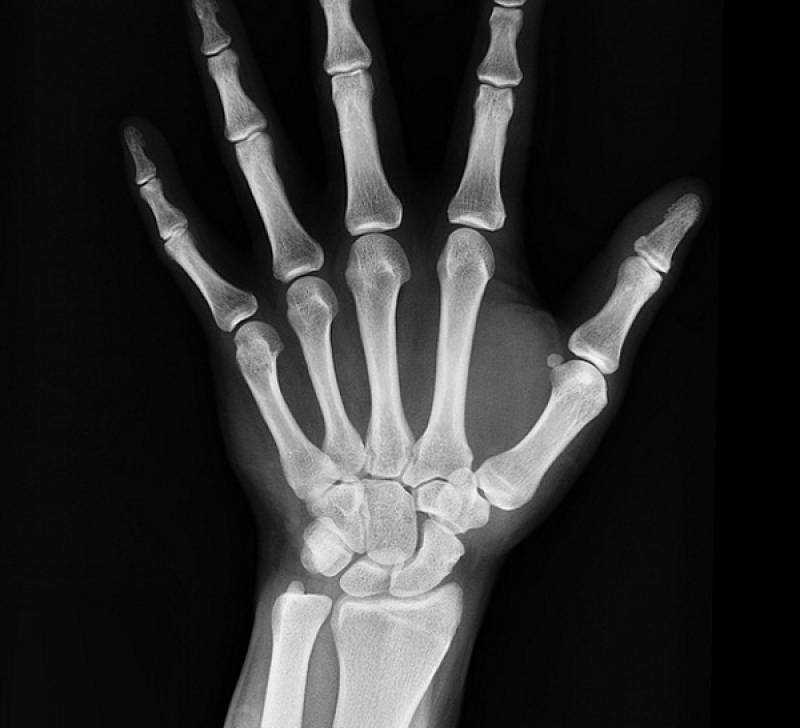

Σε κάθε περίπτωση, η "ακτινογραφία" των ελληνικών επιχειρήσεων -και κατ΄ επέκταση του ασθενούς ιδιωτικού τομέα- δείχνει ότι η ελληνική οικονομία έχει εξαντλήσει τις παραγωγικές της δυνατότητες και ότι πραγματική ανάπτυξη θα υπάρξει μόνο αν επενδυθούν τεράστια κεφάλαια για τη δημιουργία μεγάλων επιχειρηματικών μονάδων.